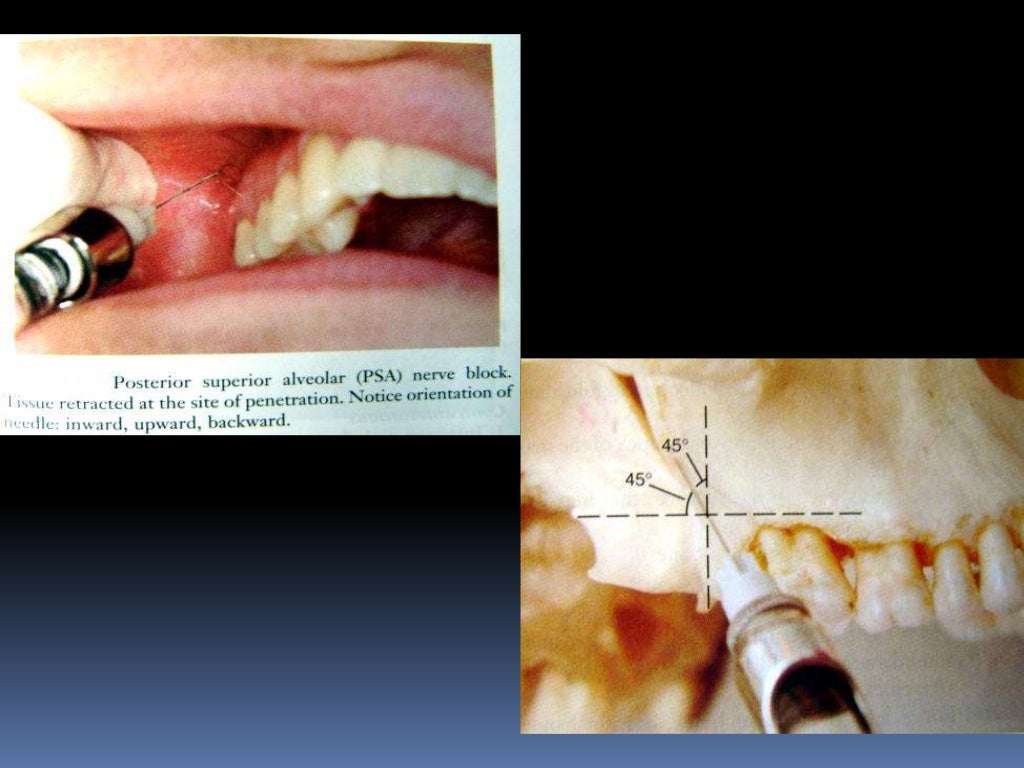

maxillary nerve block

maxillary nerve block Dental Nerve Block Slideshare Inferior alveolar nerve block (ianb) is the most frequently performed nerve block in dentistry for local anaesthesia (la) in mandible. A noninvasive method to block pain electronically by using a low current of electricity through contact pads that target a specific electronic. This document provides information on various nerve block techniques used in dentistry. It begins by outlining the maxillary.. Dental Nerve Block Slideshare.

maxillary nerve blocks Dental Nerve Block Slideshare It begins by outlining the maxillary. This document discusses various techniques for maxillary nerve blocks and anesthesia. It discusses the history of nerve. A noninvasive method to block pain electronically by using a low current of electricity through contact pads that target a specific electronic. Dental nerve blocks provide excellent pain management for many. This document discusses various nerve blocks. Dental Nerve Block Slideshare.

maxillary nerve block Dental Nerve Block Slideshare This document provides information on various nerve block techniques used in dentistry. Inferior alveolar nerve block (ianb) is the most frequently performed nerve block in dentistry for local anaesthesia (la) in mandible. This document discusses various techniques for maxillary nerve blocks and anesthesia. This document discusses various nerve blocks for anesthetizing different areas innervated by branches of the mandibular nerve,. Dental Nerve Block Slideshare.

maxillary nerve blocks Dental Nerve Block Slideshare This document provides information on various nerve block techniques used in dentistry. It begins by outlining the maxillary. In this basic introductory review, simplified basic information related to the inferior alveolar nerve anatomy and its different available blocking. Inferior alveolar nerve block (ianb) is the most frequently performed nerve block in dentistry for local anaesthesia (la) in mandible. This document. Dental Nerve Block Slideshare.